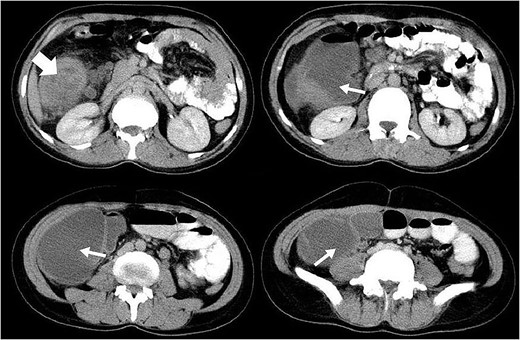

A 33-year-old Iranian female complaining of dull abdominal pain, mainly in the right lower quadrant, referring primarily to the umbilical region and epigastrium was presented to the surgical emergency department. She had also been suffering from another pain in her right flank and a mass sensation while bending her right side. The pain had a colicky pattern with a frequency of almost every 5 min. Nausea and loss of appetite were other symptoms concurrent with the main complaint that also had begun with the abdominal pain. She denied any vomiting. Although the patient remarked foamy, watery defecations with tenesmus during the recent 2 months, she had not had any evacuation or gas passing since the day before admission. She had a 4-year history of coeliac disease (CD) and anaemia, besides colon cancer in her father. Upper endoscopy revealed only decreased duodenal folds, and the biopsy confirmed the celiac disease. Ultrasonography detected a hypoechoic mass 26 × 17 × 27 mm in diameter right anterolateral to the aorta in the level of renal arteries regarding lymphadenopathy. At the same time, an abdominal CT scan reported a solid cystic mass in the paracolic region with a primary diagnosis of intussusception beside mild intestinal loops’ dilatation (Fig. 1). She underwent midline laparotomy with the preoperative diagnosis of gastrointestinal obstruction. After evacuating nearly 500 ccs of reactive serosal fluid from the abdomen, a sizeable ascending colon tumour completely obstructing the lumen attracted the operating team (Fig. 2). There was also intestinal distention and a jejunojejunal intussusception 45 cm away from the mass accompanied by diffuse mesocolonal lymphadenopathies (Fig. 3). Due to its severe attachment to the terminal ileum, ascending and transverse mesocolon, fixing it to retroperitoneum, they tended to right hemicolectomy contemporary with all regional lymph nodes dissection. The primary end-to-end anastomosis between the ileum and the remaining transverse colon was done in two layers. Then, the jejunojejunal intussusception with a margin of 10 cm from both sides was removed. Pathologic study revealed the synchronous adenocarcinomas of large and small intestines; a polypoid mucinous-type well-differentiated adenocarcinoma of the colon with mesenteric lymph node and vascular involvement contemporary with round shaped moderately differentiated adenocarcinoma of the jejunum. She was introduced to the oncologist for chemoradiotherapy. The weekly follow-ups to a month and then monthly once up to 6 months were uneventful. The events are listed in the diagram.

The axial CT scan slices of the case showing a target-shaped view (thick arrow) introducing intussusception and a distended obstructed colon with fluid accumulation distal to it due to a large mass of colon (thin arrows).